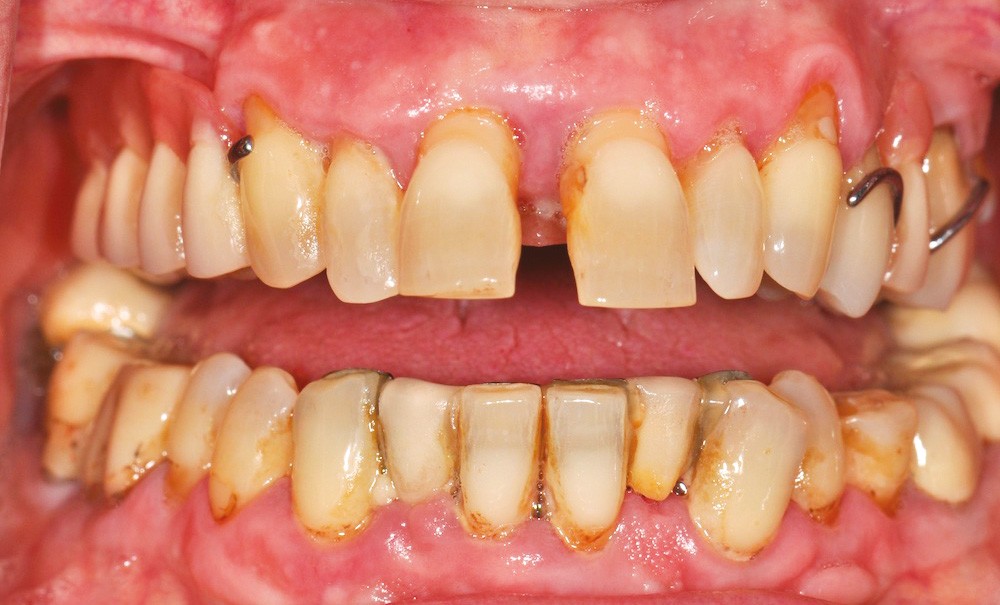

Une fois le diagnostic posé, le plan de traitement devra intégrer les meilleures preuves scientifiques disponibles, les possibilités techniques du praticien et les souhaits personnels du patient [1] (fig. 1).

Ce concept de médecine fondée sur la preuve a fait l’objet de nombreux débats et reste assez mal compris. Les données issues de la littérature (lorsqu’elles sont disponibles) sont les bases nécessaires mais non suffisantes pour prendre la bonne décision thérapeutique pour un patient donné. Les préférences personnelles de ce dernier (conception du corps et de la santé, contexte psychosocial, possibilités financières…) ainsi que les possibilités du praticien ont tout autant d’importance [2]. Le plan de traitement est donc un processus complexe nécessitant de confronter des informations diagnostiques, les souhaits et possibilités du patient et l’ensemble des options de traitement disponibles [3]. C’est la confrontation de ces trois éléments qui permet au patient, de comprendre sa situation bucco-dentaire, de connaître les possibilités de traitement (avantages, inconvénients, risques, coûts) et de formuler son consentement éclairé.

Cette approche dite socio-dentaire vise à l’amélioration et le maintien de la santé orale selon des paramètres individuels liés au patient, plutôt que sur des critères conditionnés par une vision normative du praticien [4]. Ainsi, l’abstention thérapeutique doit être considérée comme une option valable et le profil psychosocial du patient pèsera dans la prise de décision (anxiété, paramètres comportementaux…).